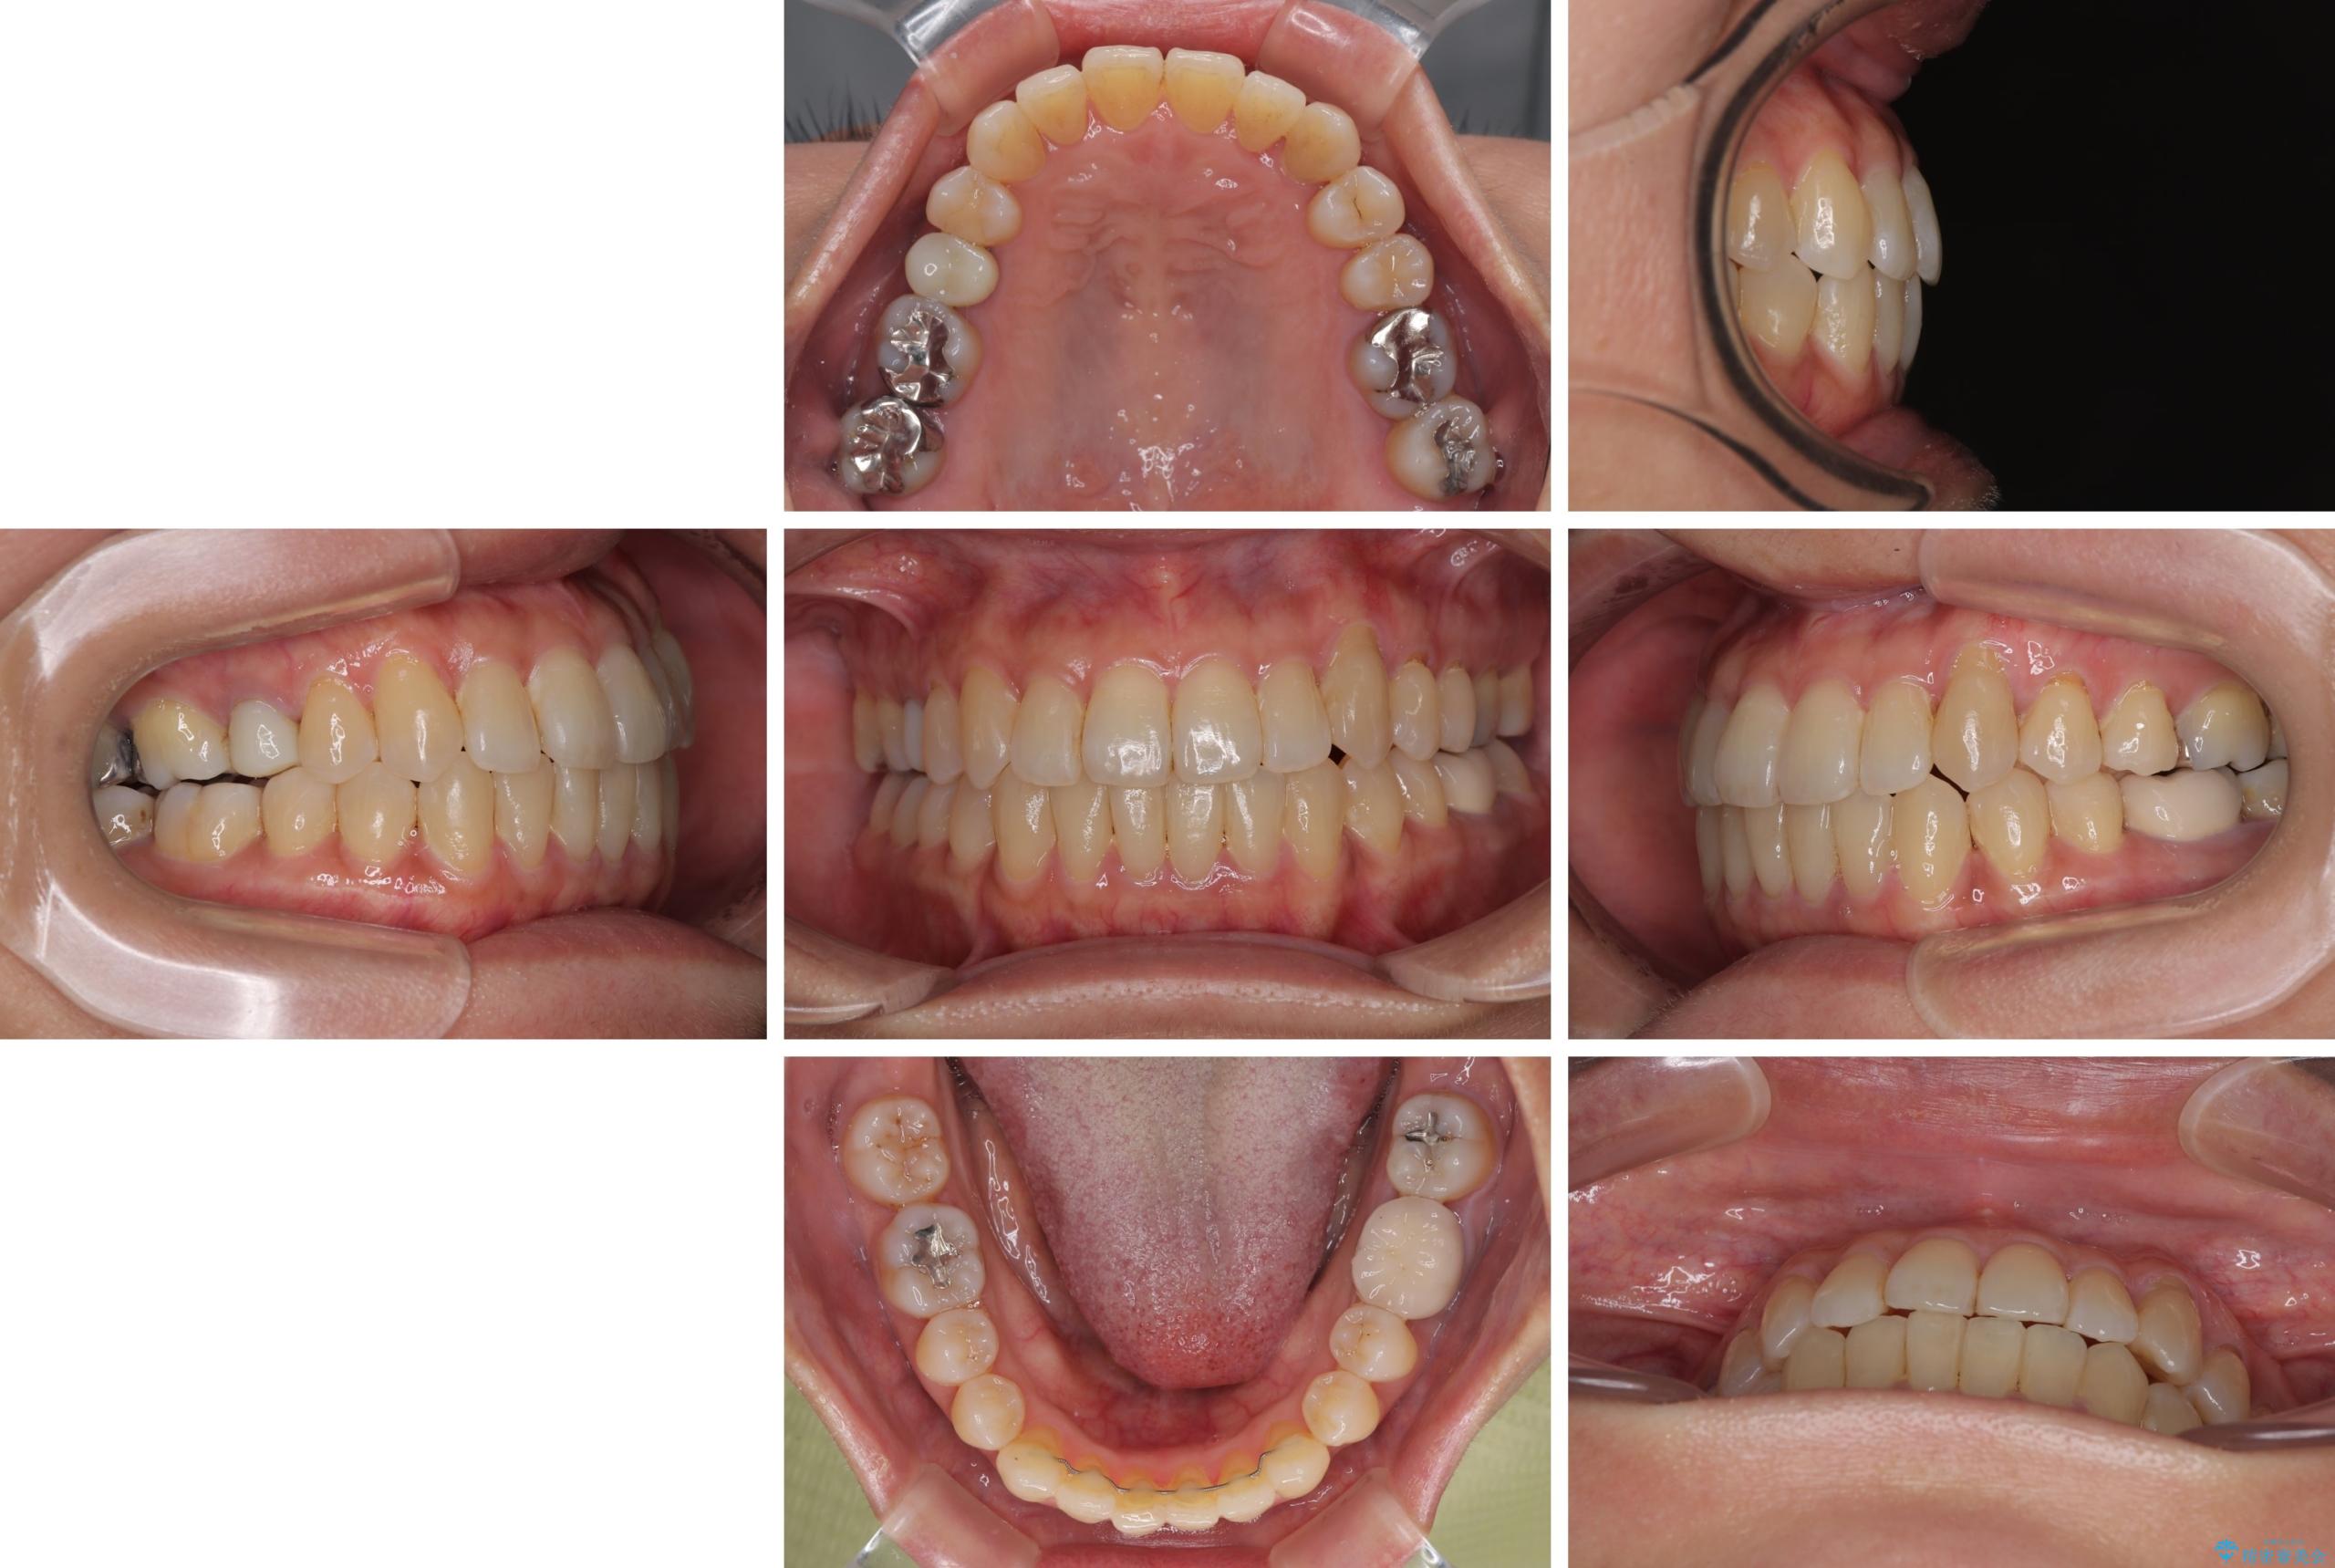

- 前歯のデコボコや八重歯を治したいとのことで来院された患者様です。

受け口傾向の骨格であり、前歯はクロスバイトまたは切端咬合となっており、下顎を中心に歯列全体の後方移動を行い、IPR(歯と歯の間を削る)によってデコボコが解消するように設計し、インビザラインにより治療を行うこととしました。

受け口傾向のインビザライン矯正は比較的治療を行いやすいため、きれいに仕上げることができました。舌の突出癖が顕著であったため、改善のためのトレーニングをしっかりと行っていただきました。